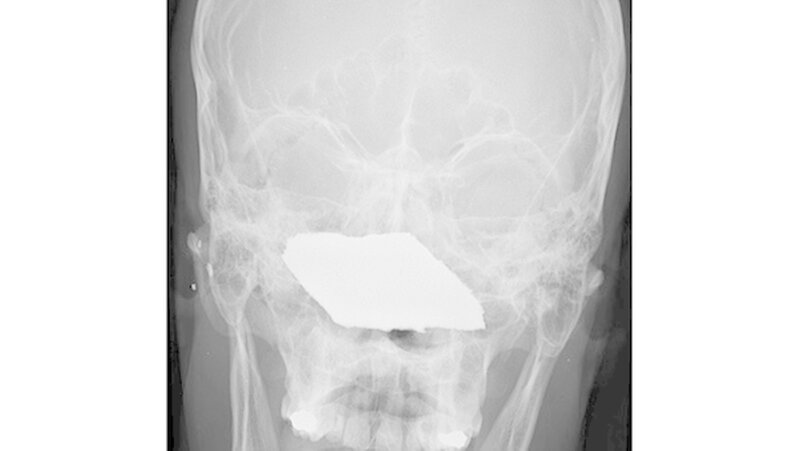

Fremdkörper im Gesicht

Vom Bohrer im Kopf bis zum Schlüssel in der Kieferhöhle: Die MKG-Chirurgen der Charité haben ausgewählte Patientenfälle mit Fremdkörpern im Gesicht zusammengestellt. In unserer Fotostrecke finden Sie die eindrucksvollen Aufnahmen.